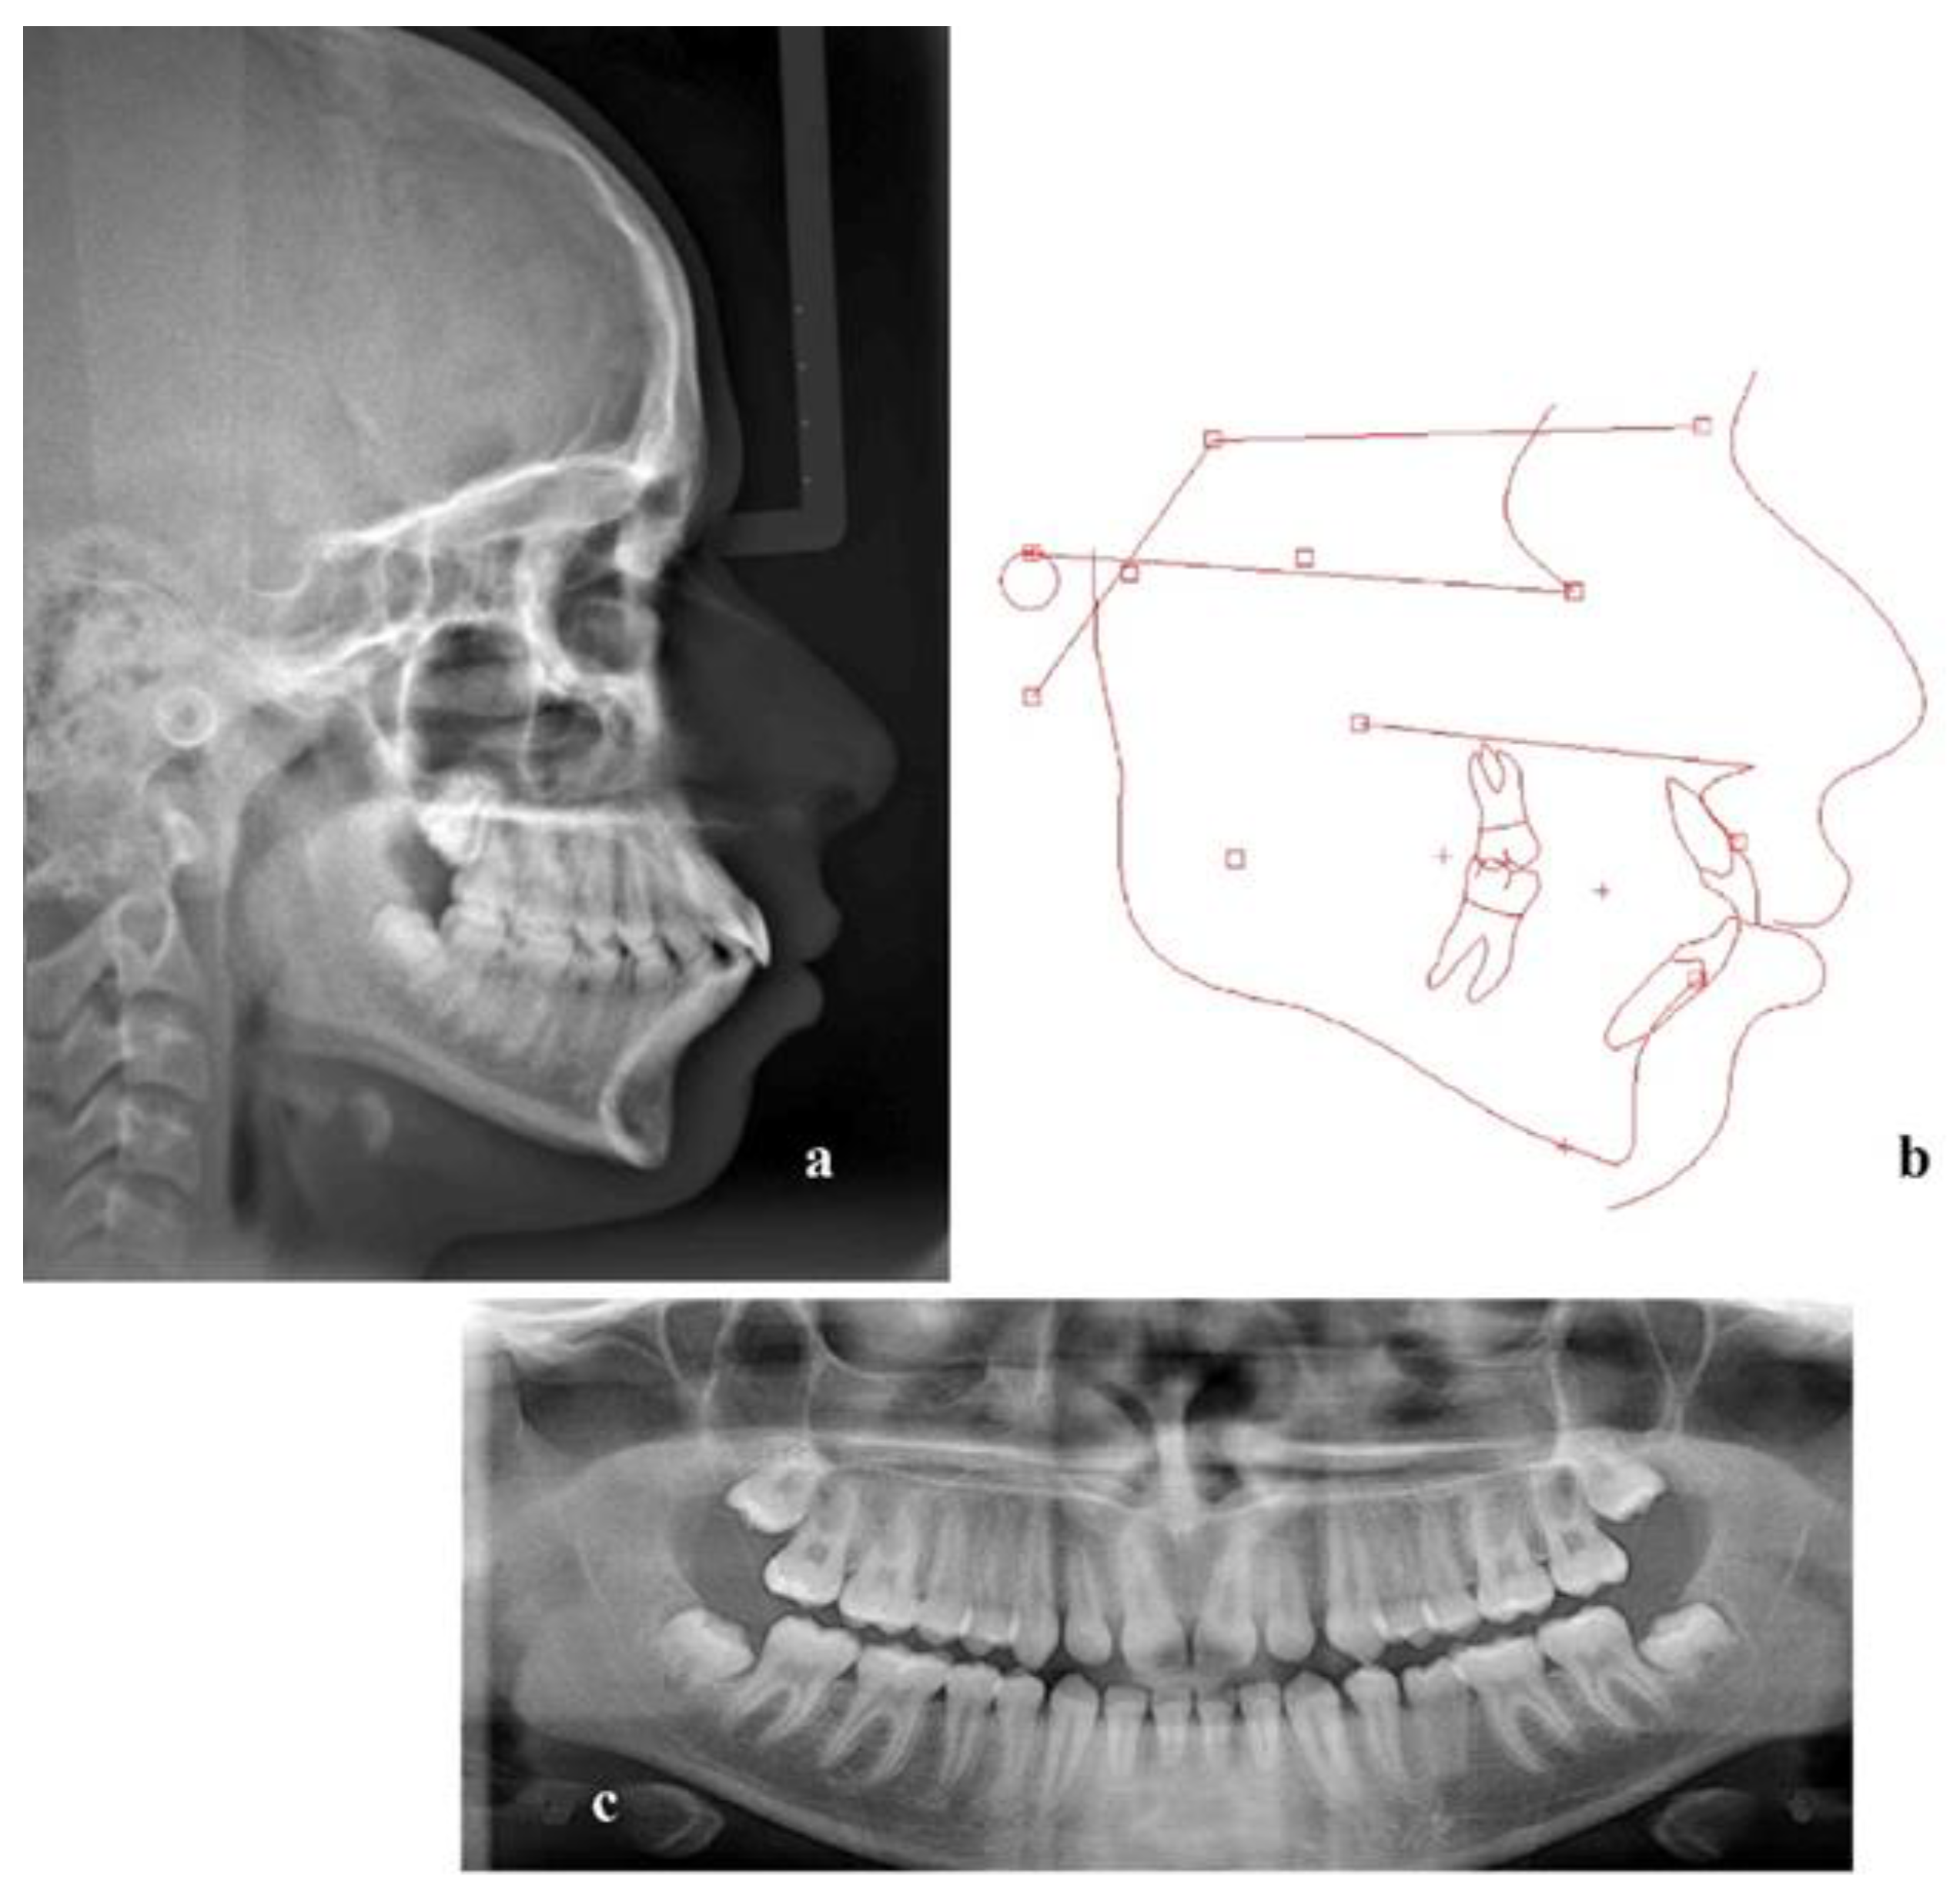

| Measurement | Mean ± SD | Pretreatment | Posttreatment |

|---|---|---|---|

| 1. SNA (°) | 81 ± 3 | 88.1 | 89 |

| 2. SNB (°) | 78 ± 3 | 83 | 84.2 |

| 3. ANB (°) | 3 ± 2 | 5.1 | 4.9 |

| 4. Wits (mm) | 1 ± 2.9 | 0.1 | 0.8 |

| 5. GoGN/SN (°) | 32.5 ± 5.2 | 27.1 | 25.8 |

| 6. U1/PP (°) | 109 ± 6 | 125.9 | 117.1 |

| 7. L1/MP (°) | 93 ± 6 | 110.8 | 94.5 |

| 8. Interincisal angle (°) | 135 ± 10 | 104.6 | 130.2 |

| 9. Labionasal angle (°) | 95.96 ± 2.57 | 106.6 | 99 |